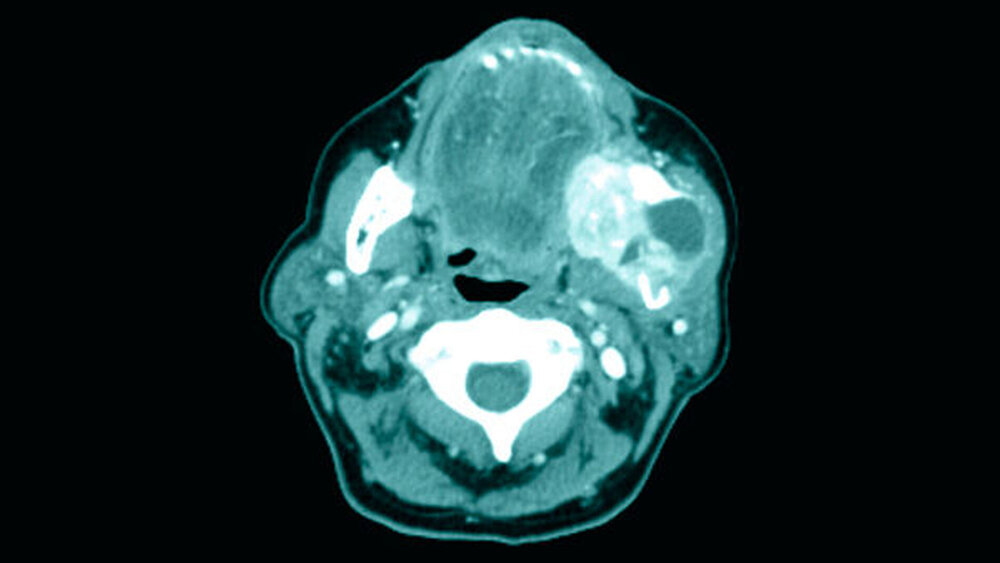

Mit dieser Diagnose wurde die Patientin zur weiteren Therapie in die Mund-, Kiefer-, Gesichtschirurgie der Universitätsmedizin Mainz überwiesen, in der das Staging mittels Computertomografie der Kopf-/Hals-Region sowie des Thorax/Abdomen komplettiert wurde. Hierin zeigte sich lokal eine Ausbreitung bis an den Processus condylaris mit bereits bestehendem Kontakt zum Sinus maxillaris (Abbildungen 4 und 5). Bei pulmonalen Verdichtungen konnte eine Metastasierung nicht sicher ausgeschlossen werden, eine abdominelle Absiedlung bestand nicht.